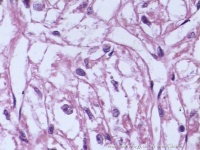

内镜下大肠脂肪瘤呈黄色质软的圆形状肿块。较大的粘膜下脂肪瘤常常突入肠腔,部分成为有蒂。活检时有时可见黄色物流出。病理可见成熟的脂肪细胞和纤维性间质出确诊。X线表现为光滑的肠腔内有蒂或广基肿块,具有形态不稳定的特征,充盈缺损可以在钡剂灌肠时随外压或排空而改变形态。